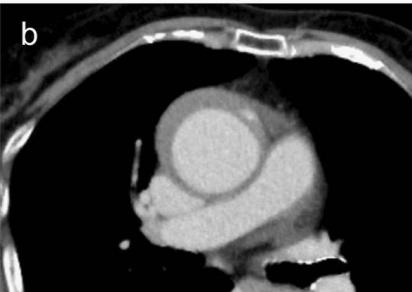

下面的CT平扫,隐隐约约基本肯定看到主动脉夹层了!

不行,你再看看,越看越像!

增强CT一看,主动脉的确裂开了!